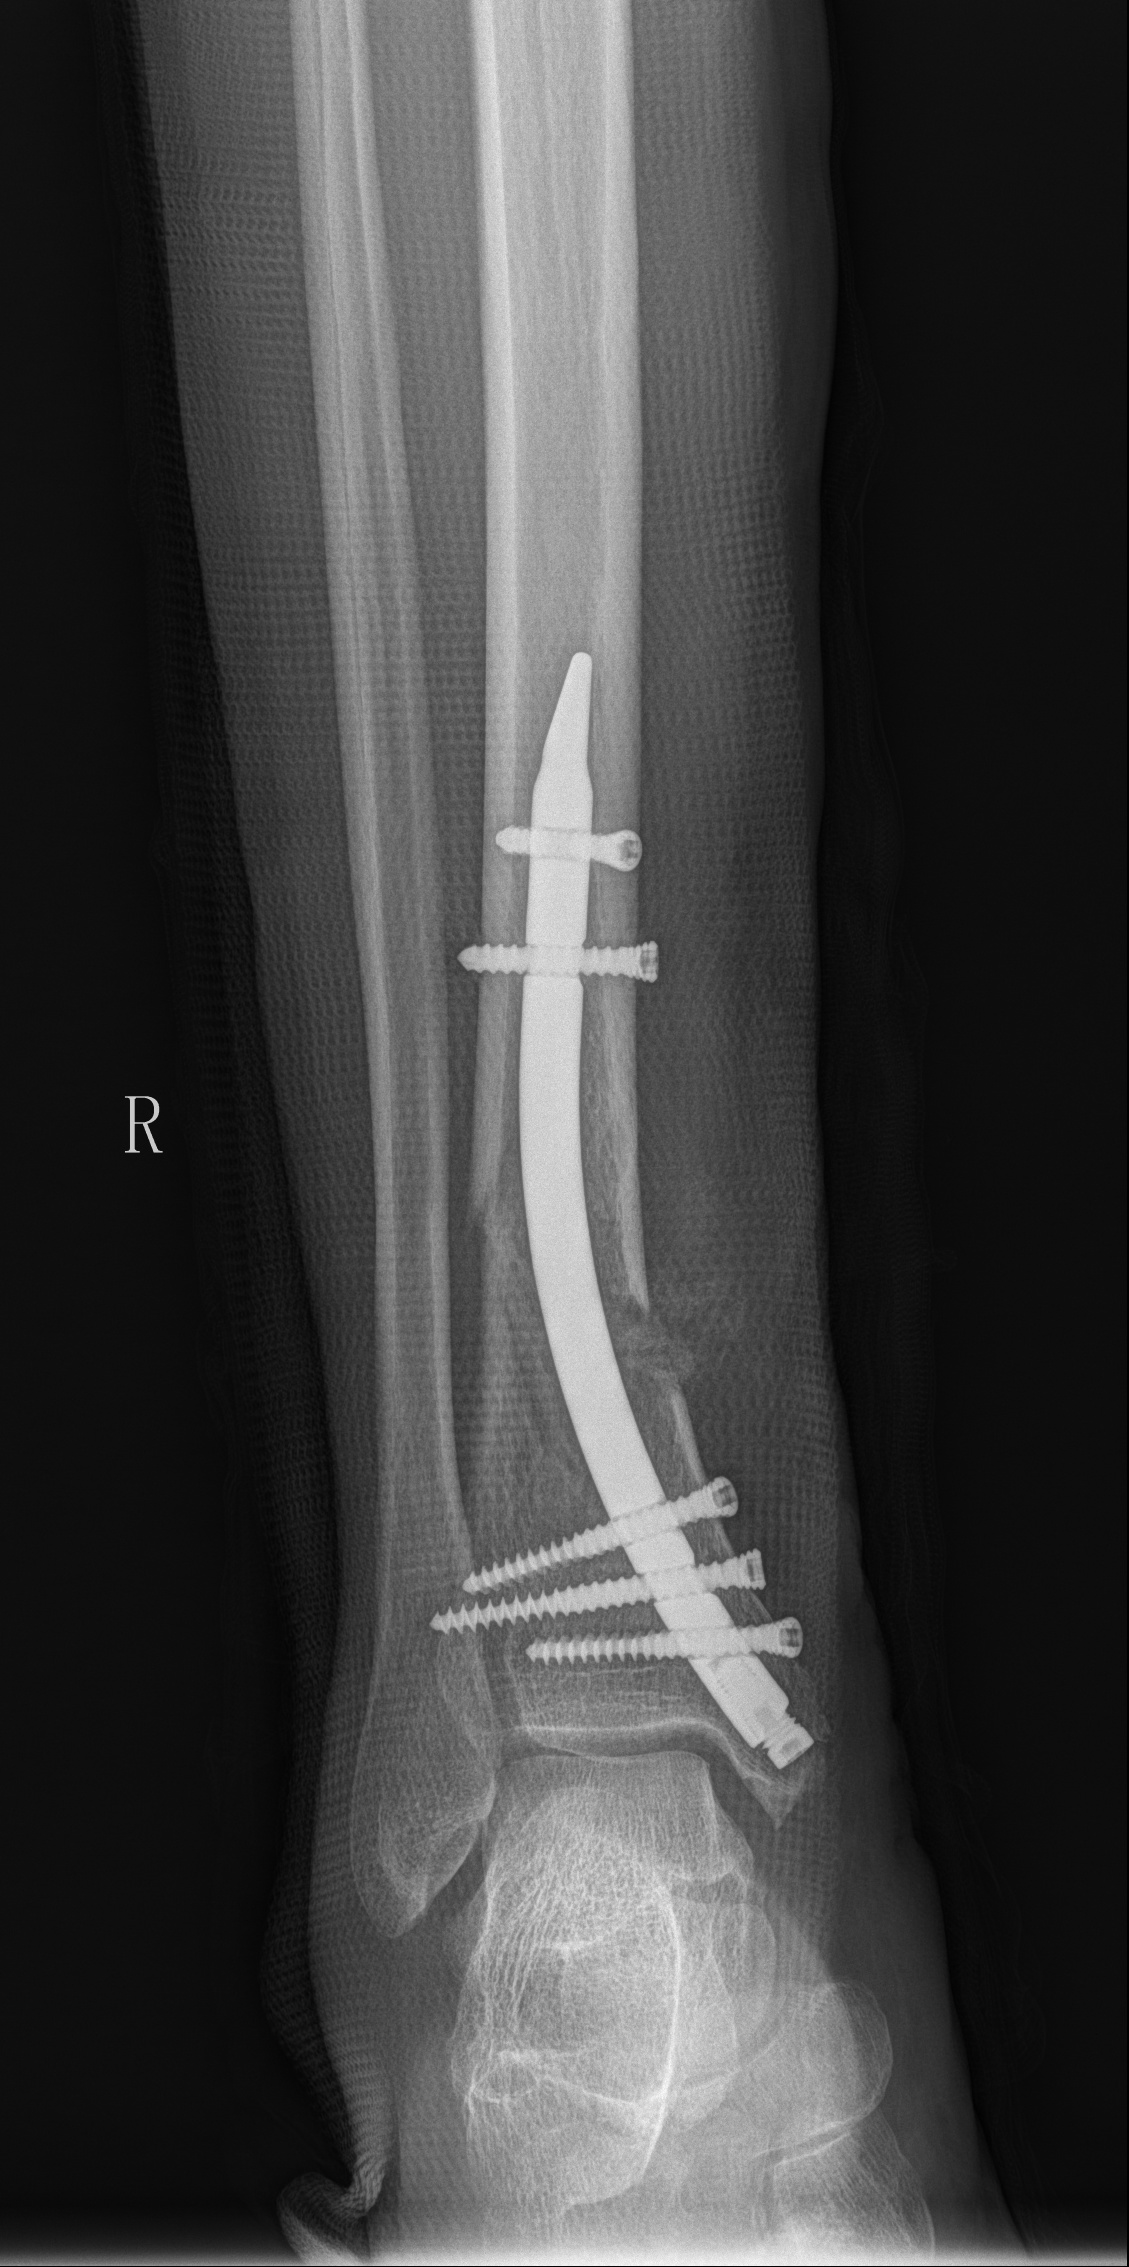

DTN术后复查右胫腓骨正侧位

近日,金瓶梅电影 创伤骨科医师团队成功完成了一例右胫骨远端开放性骨折闭合复位逆行倒打髓内钉内固定(DTN)手术,该手术是江西省内第一台胫骨逆行髓内钉手术,具有突破性意义。相比于传统手术方式,DTN具有手术创伤小,术中出血量少,切口小,手术时间短,内固定稳固,术后恢复快等优点,能迅速帮助患者减少病痛,快速进行康复。

胫骨远端骨折因其解剖结构的特殊性,容易出现软组织并发症。胫骨远端骨折可选用切开复位钢板固定、MIPPO钢板固定、胫骨顺行髓内钉固定、胫骨逆行髓内钉技术及外固定。其中切开复位及MIPPO技术手术切口较大,切口处缺乏软组织覆盖,容易出现切口感染。且钢板为偏心型固定,力学稳定性不如髓内钉的中心型固定。顺行髓内钉因骨折线位置较低远端锁钉把持力不足,同时有诱发膝前疼痛的可能。而胫骨逆行髓内钉技术作为国内逐渐发展起来的新技术,在处理胫骨远端骨折时具有软组织损伤小、复位及固定简易等优势,十分适合本患者。